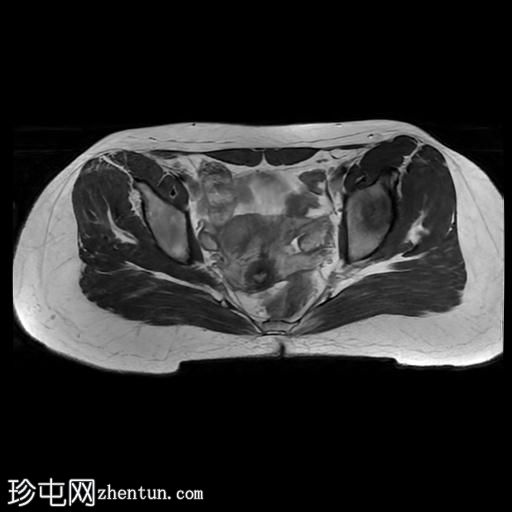

MRI

轴位

T1加权像

轴位T2加权像

臀中肌髂骨起点处前侧全层撕裂,伴有充满液体的间隙,以及髂骨髓水肿。

MRI结果符合臀中肌近端髂骨起点处全层撕裂的

影像

学表现。